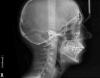

omeza Опубликовано 23 июня, 2010 Автор Поделиться Опубликовано 23 июня, 2010 Долгожданное ТРГПрокомментируйте пожалуйста уважаемые ортодонты! Ссылка на комментарий

Force Опубликовано 28 июня, 2010 Поделиться Опубликовано 28 июня, 2010 соглашусь с удалением, на Damon будет относительно быстрее и благоприятнее для парадонта, Что за чушь? Брекеты Деймона не ускоряют процесс лечения как и любая другая система. По поводу пародонта - тут вообще спорный момент. Чем они лучше? Научных данных нет, есть как раз наоборот. Пациентке: по поводу ТРГ - все без изменения. Намеченный план не изменяется. Ссылка на комментарий